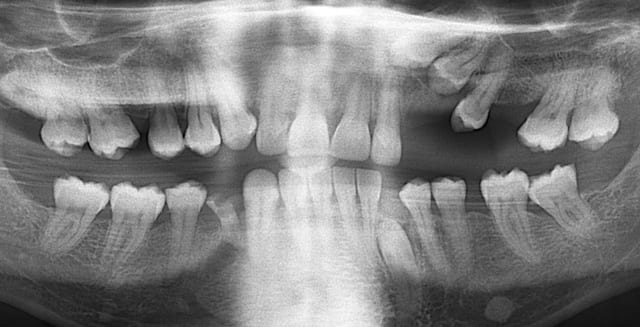

L’orientation vestibulaire ou palatine d’une canine est indiquée par son inclinaison sur la téléradio. Si elle apparaît horizontale sur la radio elle est en direction vestibulaire, par contre elle sera palatine si elle apparaît verticale. A compléter bien sûr par l’examen de la pano. Cela suffit dans la très grande majorité des cas pour situer une canine et aller la chercher.

Ici, elle est manifestement vestibulaire et c’est bien là que je l’ai trouvée.

Petite colle facile :

Cette 13, on va la chercher en vestibulaire ou en palatin ?

10542 07 05 02bis klstyw - Eugenol

ne serait-elle pas palatine avec la face vestibulaire orientée en palatin?

on devine une forme de cingulum vers l'avant sur la télé, non?

Elle est effectivement bien palatine.

Tu as peut-être raison pour la rotation bien que cela m'étonne car je l'aurais noté. En réalité je ne me souviens plus et la photo prise per-op ne le montre pas..